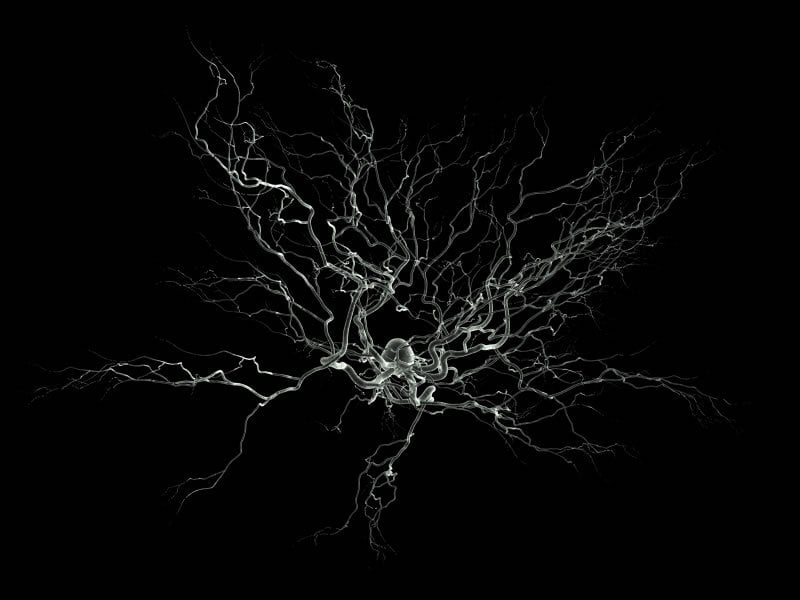

Image Source: The image is credited to Nicolas P. Rougier and is licensed under the GNU General Public License.